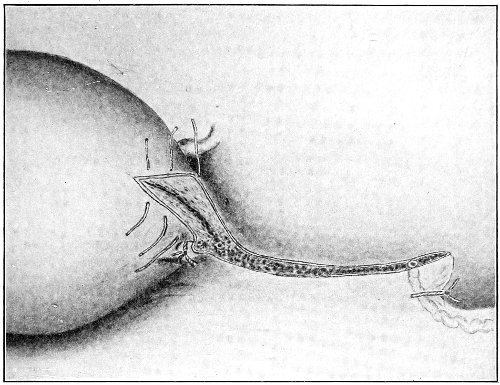

The secondary operation is performed at any time after cicatrization has occurred—often many years after the receipt of the injury. This operation is at present one of the commonest in gynecology, because the injury is not detected, is neglected, or is improperly repaired after labor. In the secondary operation an anesthetic is necessary. The mucous membrane must be removed or denuded on the posterior wall and about the mouth of the vagina, in order that the lacerated structures may be brought again in apposition. The denudation is best made by means of scissors curved on the flat (Figs. 24 and 25).

The strip of mucous membrane to be removed is picked up with a tenaculum (Fig. 26) or with tissue forceps 65 (Fig. 27); the scissors are placed with the blades parallel to the surface to be denuded, and the strip is cut away evenly, in one piece if possible. A similar contiguous strip is removed, and so on until the necessary surface is bare. Sponges in holders (Fig. 28) or continuous irrigation may be used to remove blood.

Slight Median laceration of the Perineum.—In this injury the tear takes place through the fourchette. Posteriorly it may extend as far as the sphincter ani muscle. Upward it may extend for an inch up the posterior vaginal wall. The appearance of this tear is shown in Fig. 33. It will be noted that, as this tear takes place in the median line, none of the muscles that support the perineum are involved, nor are the planes of fascia injured. The perineum is slightly split, and the insertions and origins of the muscles and the fascia are slightly separated. The supporting structures of the perineum and the pelvic floor are, however, uninjured.

Fig. 33.—Recent slight median laceration of the perineum: sutures introduced.

If this tear is detected after labor, it should be closed by the immediate operation. A slight tear involving chiefly the cutaneous aspect of the perineum should be closed by three or four sutures introduced from the outside, as in Fig. 33. The needle should be introduced about a quarter of an inch from the edge of the wound. It should not be passed parallel with the plane of the lacerated surface, but should be swept outward and then inward toward the 68 angle at the bottom of the tear (Fig. 34). It may either emerge at the angle and be re-introduced, or it may be passed directly through to the skin-margin on the opposite side of the wound. If the suture is passed in this way, there will be perfect apposition throughout the whole surface of laceration. If the sutures are improperly passed, there may result only apposition of the skin-edges.

Fig. 34.—Diagram representing the correct and the incorrect method of passing the suture for closure of slight perineal laceration.

If the laceration extends up the posterior vaginal wall, two sets of sutures must be introduced—one on the vaginal aspect of the tear, and one on the skin aspect (Fig. 35).